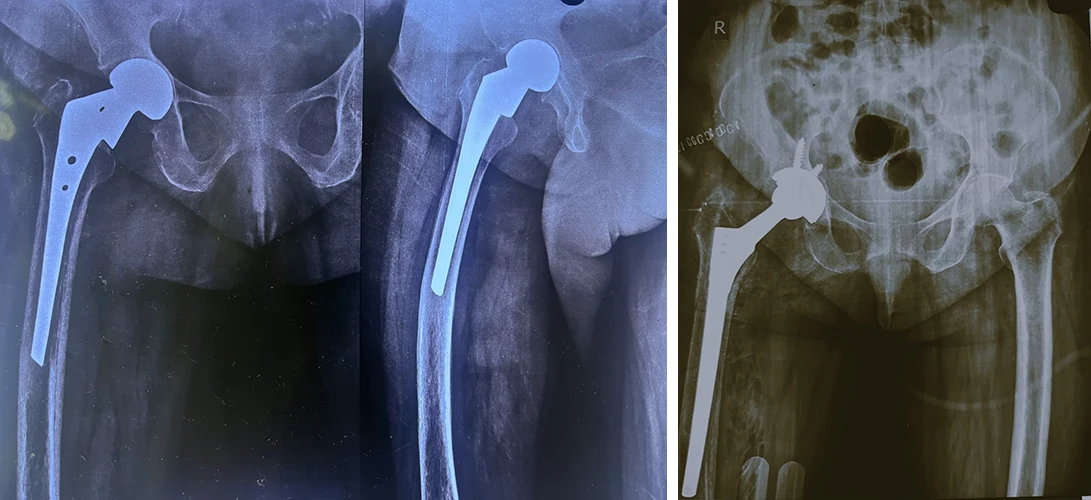

Total Hip & Knee Arthroplasty

Total Hip Replacement

Are your hips causing you constant discomfort? If you're tired of living with hip pain, Dr. Prasun Sanyal is your best solution.